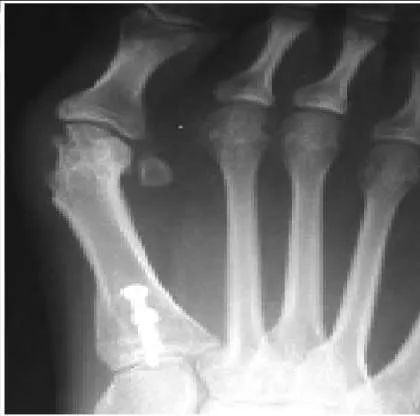

A 59-year-old woman presents for treatment of a painful hallux valgus deformity. She has a prominent bunion, normal motion of the hallux metatarsophalangeal (MP) joint, and painful callosity under the second MP joint. Radiographs of the foot are presented. The recommended treatment is:

Explanation:

This patient has probable instability of the metatarsocuneiform joint manifested by the overload phenomenon of the second metatarsal. Although this is not a sufficient indication for performing an arthrodesis of the metatarsocuneiform joint (modified Lapidus procedure), other findings of second metatarsal overload, including thickening of the cortex of the second metatarsal and instability of the first metatatarsocuneiform joint, should be looked for in addition to hypermobility of the first ray.